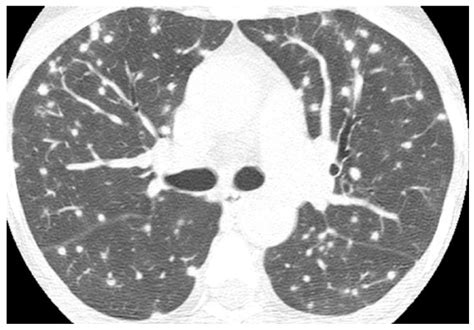

• High-Resolution CT (HRCT): Provides detailed images of the lung parenchyma, useful for diagnosing interstitial lung diseases.

CT of Thorax in Lung Cancer Screening

One of the most significant applications of the CT of thorax is in lung cancer screening. Early detection of lung cancer can significantly improve survival rates. The procedure is particularly beneficial for individuals at high risk, such as:

Regular screening with a CT of thorax can help detect lung nodules or masses at an early stage, allowing for timely intervention and treatment.